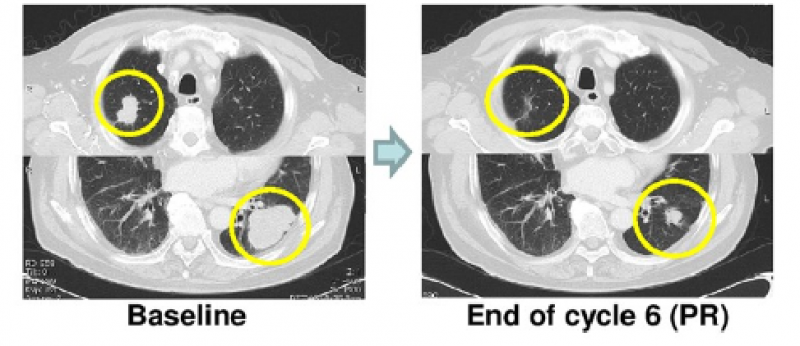

77岁男性,RAS野生型转移性直肠癌,MSS, PD-L1 CPS=0。FOLFIRI+Bevacizumab, FOLFOX, irinotecan+cetuximab,trifluridine/tipiracil后进展接受O药联合瑞戈非尼治疗后病情迅速缓解。